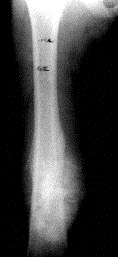

病历摘要: 患者 ×××,男性,9岁,右大腿下段肿痛3个月。查体:T 36.7℃, P 80次/分,右大腿下段皮肤肿胀,血管恕张,触痛(+),质硬,叩击痛...

问题 病历摘要: 患者 ×××,男性,9岁,右大腿下段肿痛3个月。查体:T 36.7℃, P 80次/分,右大腿下段皮肤肿胀,血管恕张,触痛(+),质硬,叩击痛(+),其余(-)。实验室检查:ESR 20mm/L。 该患儿的治疗以下叙述正确的是?

选项 A、瘤段节段切除以踝代膝 B、瘤段节段切除+安装肿瘤膝关节假体 C、右大腿截肢 D、局部DSA灌栓塞化疗 E、瘤段节段切除+携带监测皮岛的腓骨与异体骨移植 F、先全身化疗